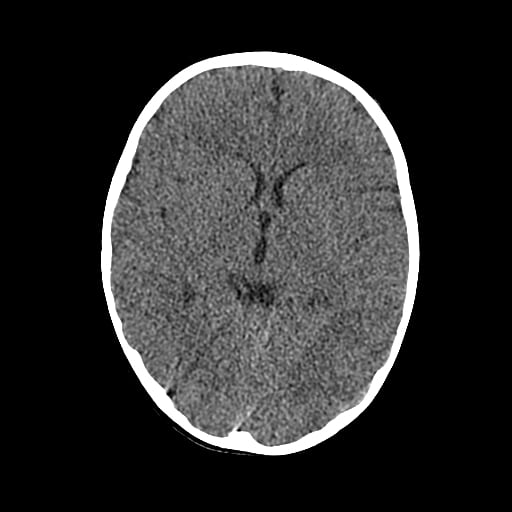

Age: 1

Sex: Male

Indication: Fall